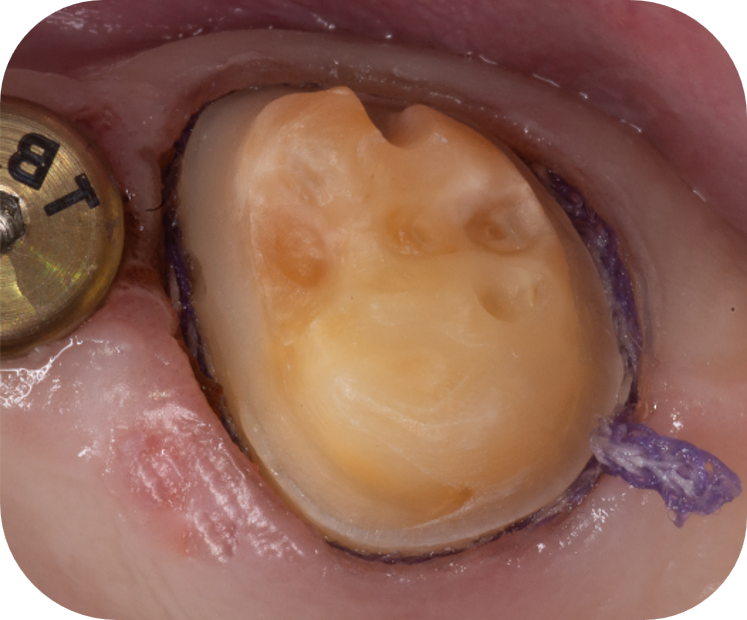

Retraction cord ​placed (Slide 25, IRC7)

Retraction cord removed, sulcus opened, no bleeding (Slide 28)